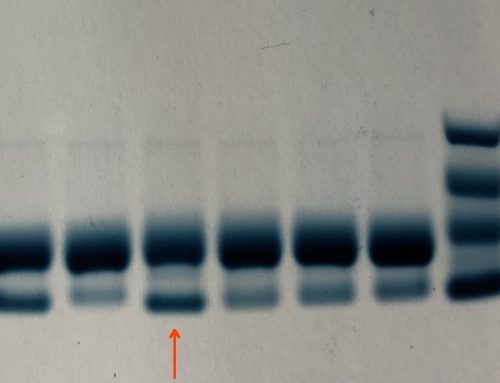

Protein S 10%